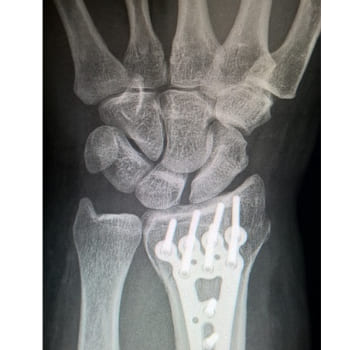

손가락 관절염 치료는 수술을 하지 않고 하는 치료와 수술 치료가 있습니다. 또한 퇴행성 관절염 치료법은 웬만하면 수술까지 가지 않아도 상태를 호전시키거나 완치할 수 있습니다.

퇴행성 관절염 치료법의 대표적인 비수술적 치료는 약물 치료와 주사 치료, 그리고 체외 충격파 치료가 있습니다. 이 외에도 고강도 레이저 치료, 도수 치료 등이 있습니다.